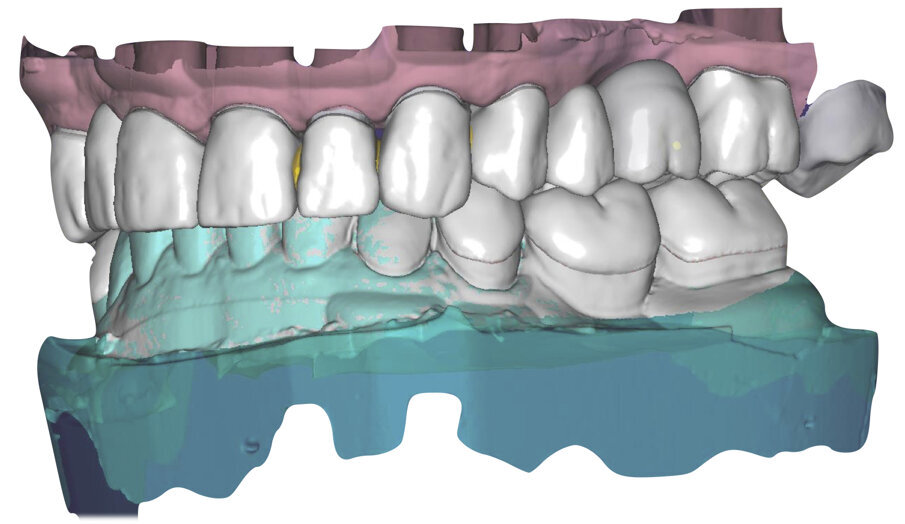

I modelli sono così importati in corretta posizione spaziale tramite il modulo exocad Virtual Articulator (Fig. 25). Non avendo a disposizione nel CAD l’analogo virtuale dell’articolatore Reference SL, viene impostato il sistema virtuale SAM, che usa lo stesso piano di riferimento axio-orbitale e geometria sovrapponibile al Reference SL. Per la programmazione virtuale dei parametri funzionali dell’articolatore si riesegue l’output dall’axiografia elettronica con Gamma Dental per SAM (Fig. 26). Si procede perciò ora con la modellazione CAD della ceratura mantenendo il riferimento dato dal piano occlusale individuato dai coni di centrica scansiti con l’articolatore (Fig. 27). L’articolatore virtuale consente una prima verifica dei rapporti occlusali tra gli elementi e un abbozzo di funzionalizzazione delle cuspidi con strumenti virtuali dinamici, che permette di arrivare ad un CAD design vicino alla morfologia ricercata (Figg. 28-33). Il modellato è ora fresato in cera Yeti Dental al CAM con fresatore VHF Cam5-S1 ed i denti in cera, tutti singolarmente sfilabili, sono posizionati sui modelli eseguiti con stampa 3D.

Il fresato ottenuto è poi riportato su articolatore Reference SL – già opportunamente programmato – e viene dall’Odontotecnico competente più precisamente funzionalizzato secondo i criteri della programmazione funzionale sequenziale, evidenziando con cere colorate i rapporti di centrica, le funzioni di mediotrusiva e protrusiva e le protezioni retrusive. I monconi sfilabili consentono la modellazione della sequenzialità mediotrusiva con la guida incisale indicata dalla registrazione axiografica (blu) (Figg. 34-37). La ceratura sequenziale è ora scansita con Sirona InEos X5 su Exocad, ed il modellato viene ricontrollato al CAD per spessori, connessioni e morfologia, e nella regolazione degli offsets per la ripreparazione dei monconi, ed è inviato al CAM per la fresatura dei II provvisori in Bredent breCAM.multicom, un PMMA con microriempitivo ceramico ad alta stabilità, su Dental Plus 5 Axis Milling Machine. La rifinitura dei monconi è seguita da ribasatura dei II provvisori in TRP - previo isolamento di tutte le superfici funzionali - e gli stessi sono poi rifiniti e lucidati. I soli elementi 3.3, 4.2 e 4.3 sono rimodellati in regione incisale con addictions in composito, secondo la morfologia studiata in ceratura. La consegna conferma la buona integrazione dei manufatti dal punto di vista estetico, occlusale, articolare e neuromuscolare, con controllo occlusale conforme al progetto (Figg. 38-42).

Il paziente utilizza questi secondi provvisori per otto settimane, durante le quali conferma la buona integrazione dei restauri e la soddisfacente funzione occlusale. Ciò è verificato con l’esecuzione di una nuova axiografia elettronica che già a due settimane dalla consegna evidenzia una buona risposta muscolare al nuovo design occlusale ed alla nuova postura mandibolare in TRP (Figg. 43-46). Provvediamo infine alle impronte per la costruzione dei manufatti definitivi in Zirconia-ceramica. I modelli sono scansiti in laboratorio con inEos X5 (Dentsply Sirona) su exocad (Figg. 47-49), ed una seconda scansione viene eseguita con i provvisori del Paziente posizionati sui modelli (Figg. 50-52). Il CAD consente di eseguire un matching fra le due scansioni, per cui i secondi provvisori utilizzati in TRP, con funzione occlusale sequenziale già completamente programmata, sono utilizzati per definire le morfologie dentali definitive di tutti gli elementi da restaurare (Figg. 53, 54) secondo il rapporto intermascellare definito (Figg. 55-58). Si esegue quindi fresatura al CAM della protesi definitiva in zirconia (Figg. 59, 60), la stratificazione e finitura ed infine la consegna al Paziente con cementazione in Panavia V5 (Figg. 61-65).